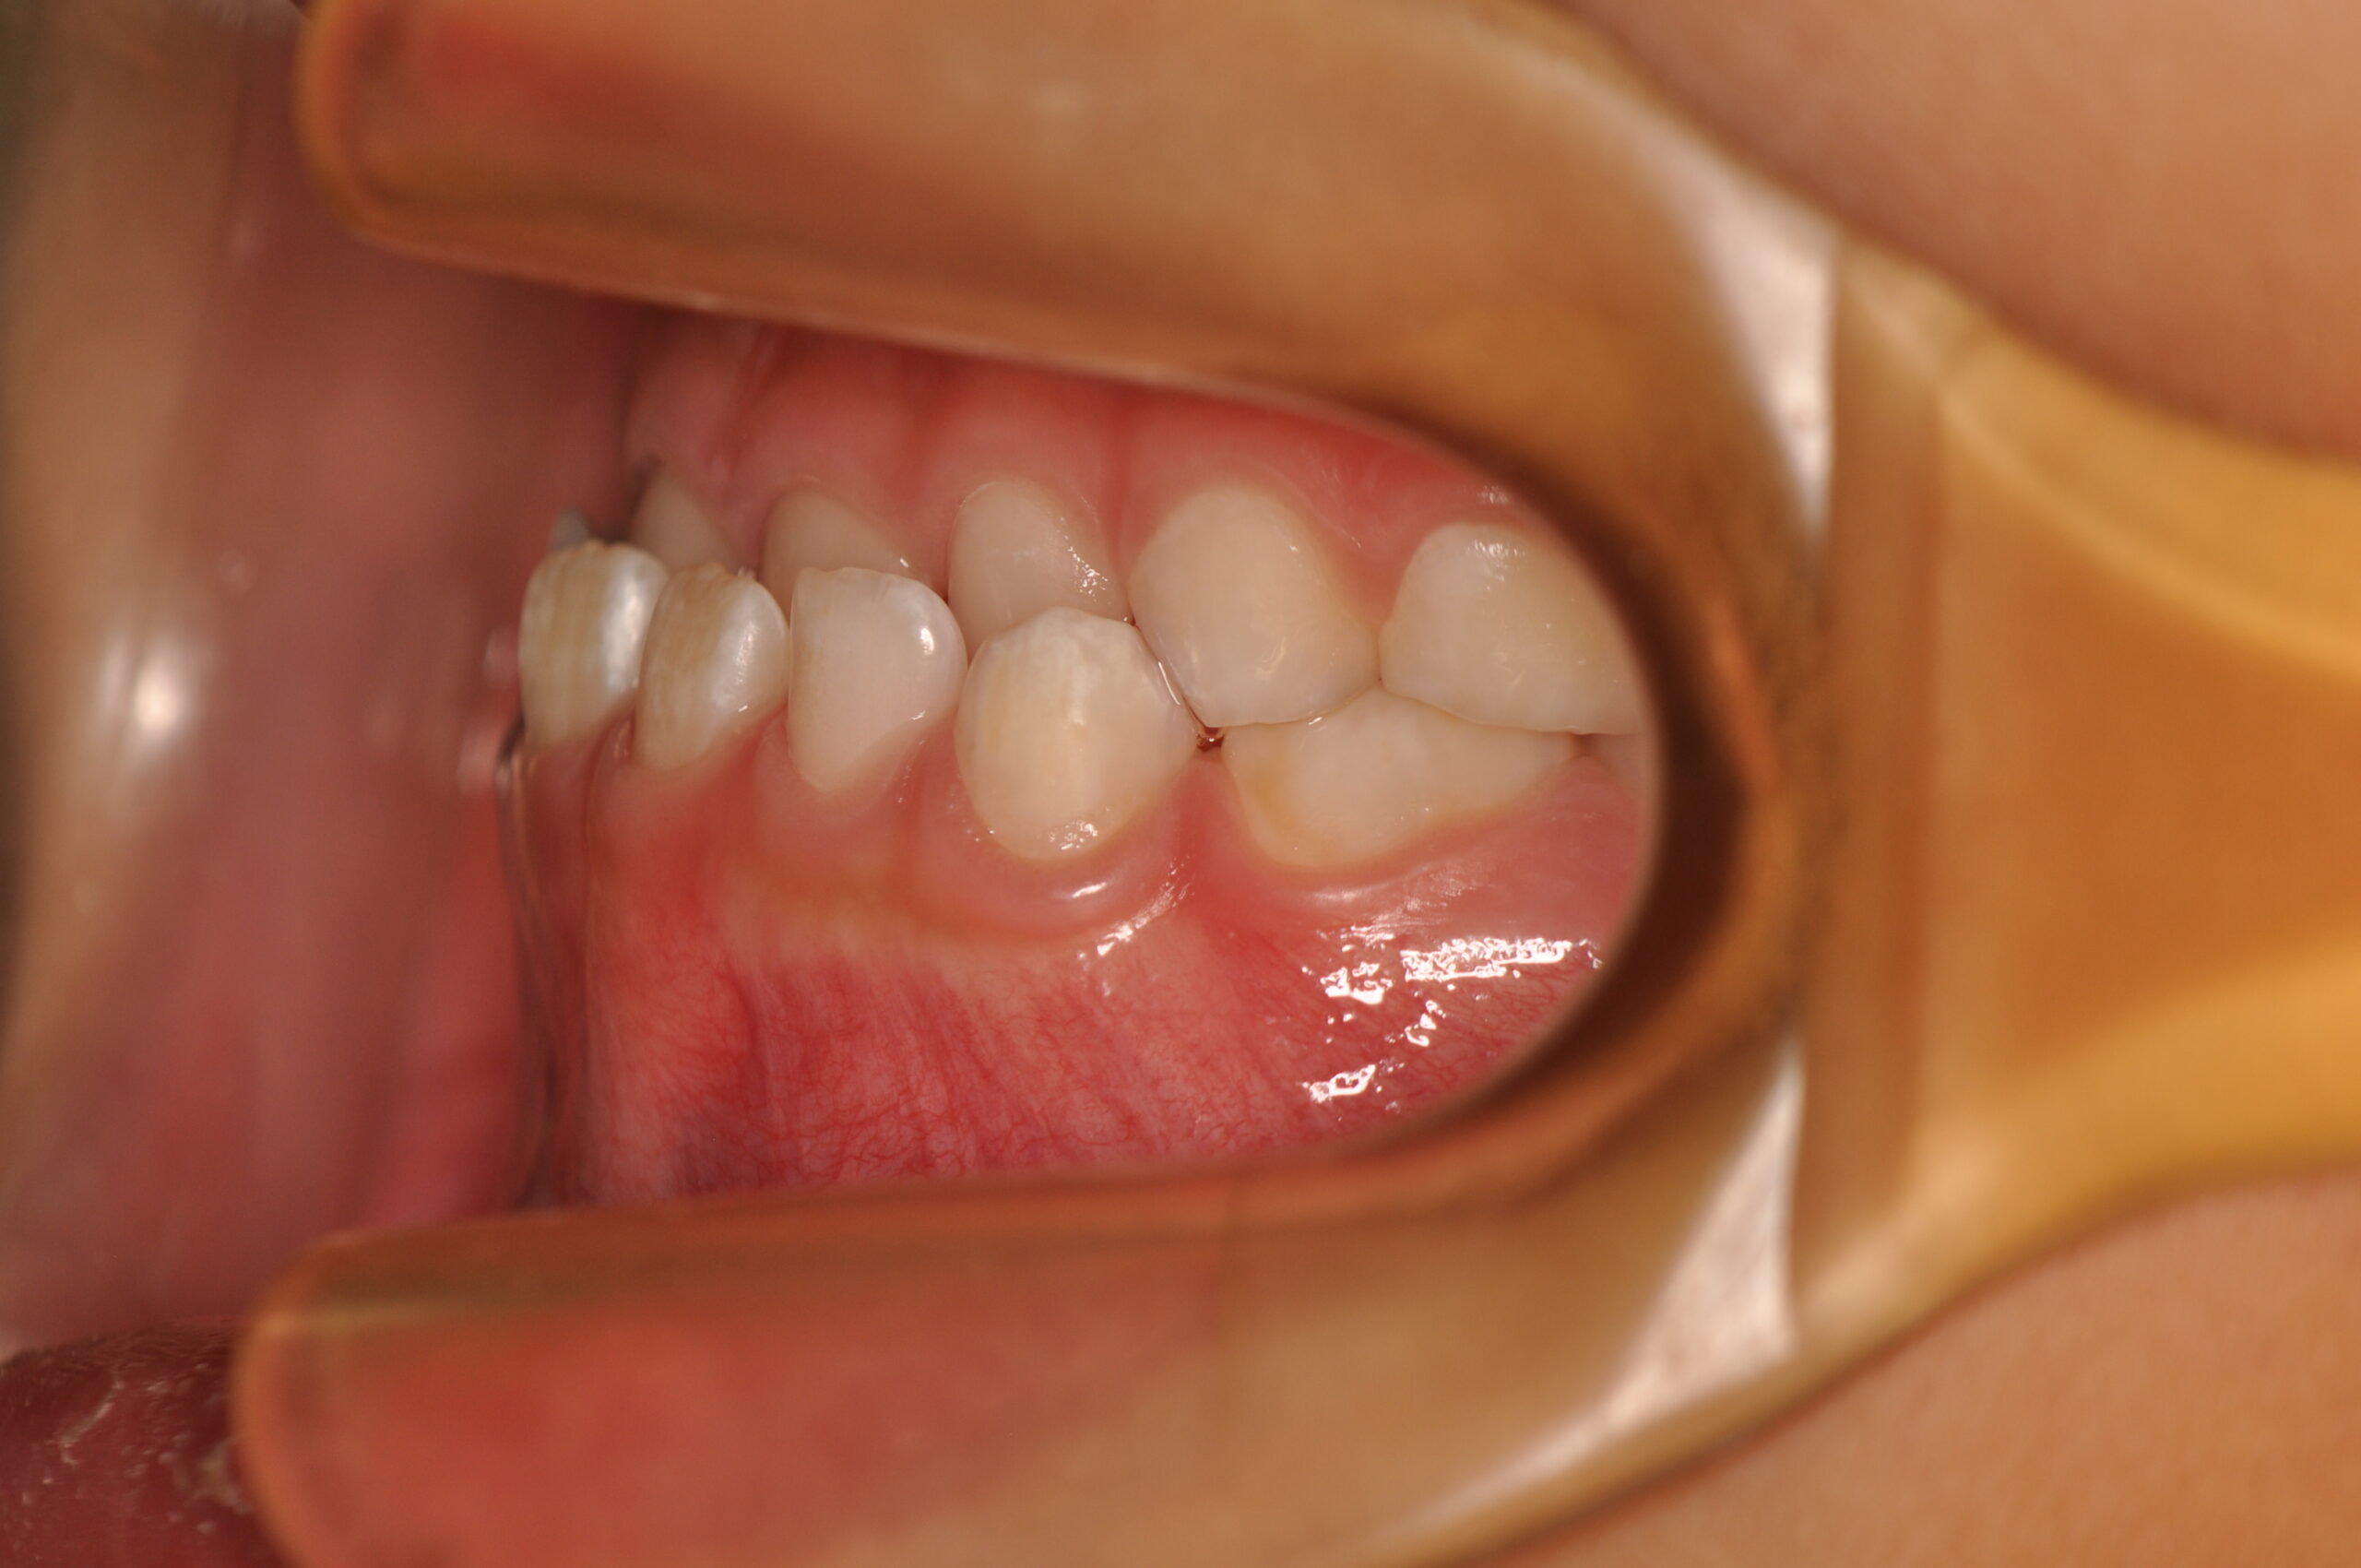

動的治療終了時

症例 症例 症例 症例

治療としては、初期段階の治療として、機能的矯正装置で鼻呼吸の獲得と舌の位置や口唇の閉鎖といった筋機能習癖の改善を行い、上顎前方牽引装置を使用し上顎骨の前方方向への発育を誘導し、反対咬合の改善を行いました。

永久歯列に交換後、非抜歯の上、セルフライゲーションブラケット装置(デーモンシステム)で歯の配列と咬合関係の改善を行いました。